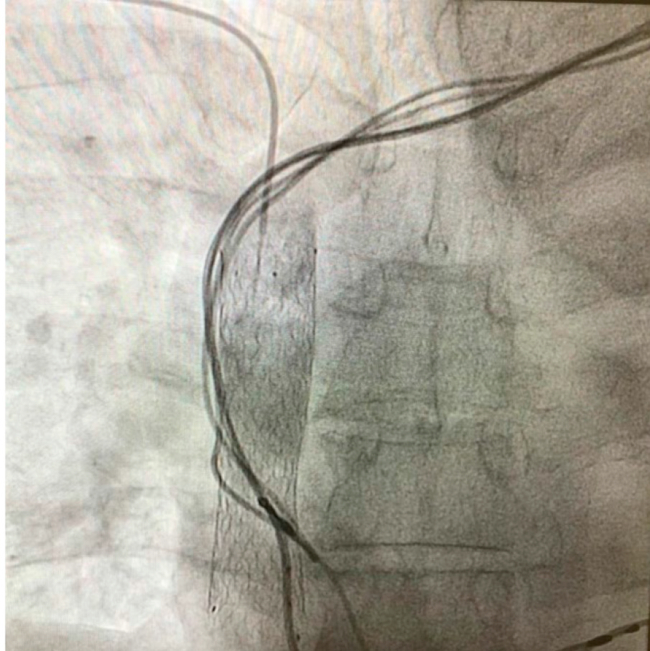

Dados el cuadro infeccioso y la coexistencia de tres catéteres atrapados por el stent en la VCS, se resolvió la extracción de todo el sistema de estimulación, en un paciente dependiente de la estimulación. Se realizó una cavografía, a fin de analizar la permeabilidad del stent (Figura 1) y una tomografía multicorte para planear la estrategia de extracción quirúrgica (Figura 2). Se resolvió realizar una cirugía de extracción combinada, abierta por esternotomía mediana, con circulación extracorpórea y clampeo aórtico, y por vía percutánea a través del bolsillo izquierdo de implante del generador. A través de la auriculotomía, se identificó el stent que avanzaba dentro de la aurícula derecha, y se liberaron los tres catéteres endocavitarios del ventrículo derecho y de la aurícula hasta el stent dentro de la VCS. En forma simultánea y por vía percutánea, se liberaron los tres catéteres del tejido fibroso de la región subclavia e innominada izquierda, hasta llegar al borde proximal del stent. Se utilizaron estiletes, liberador y vainas de polipropileno Cook® de 10 Fr. Dos de los catéteres fueron seccionados por encima del stent y extraídos a través de la aurícula, y el tercero, que fue seccionado en la aurícula, se extrajo a través del bolsillo. El catéter epicárdico fue seccionado a ras del pericardio y extraído desde el bolsillo.